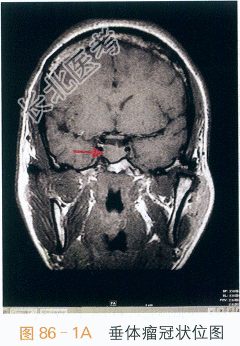

- [材料题] 患者,女性,50岁,因“手足进行性肥大10年余,咽部哽噎感1年半”入院。患者10年前无明显诱因出现双手中指指间关节肿大伴屈曲疼痛,腰痛明显,无发热、晨僵、口腔溃疡及光过敏现象,遂于当地医院就诊,行风湿免疫学检查未见异常(具体报告未见),未予治疗。7年前出现双手指间关节及双足掌趾关节增大、增粗,伴双手、双足增大、肥厚,呈进行性加重(1年内鞋码由36增大至39码),自觉多汗、怕热、易倦,无头疼,无视物模糊及视野缺如,无泌乳,无多尿、多饮、多食,无消瘦,无胸闷、胸痛,多次于当地医院就诊,3次查风湿免疫指标未见异常(具体报告未见),未予处理。查血尿酸水平,未见异常(具体报告未见)。1年半前无明显诱因出现咽部哽噎感,自觉上腭饱满、唇舌增厚、吐字不清,伴呼吸不畅,睡眠时症状明显,但可平卧入睡,偶有夜间憋醒,坐位后缓解,情绪激动时偶有胸闷,持续2~3min后自行缓解,无心悸、胸痛、头痛,无吞咽困难、饮水呛咳,无嗜睡,反复就诊于当地耳鼻喉医院,诊断为“鼻窦炎”,给予曲安奈德喷雾剂、头孢氨苄等治疗后,咽部哽噎感无好转。于五官科医院行鼻窦轴位CT平扫。十冠状位重建示:右侧前组筛窦、上颌窦慢性炎症,鼻中隔偏曲,右侧鼻腔低密度软组织影。1年半以前于五官科医院行喉镜检查未见明显异常。1年前再次于五官科医院行喉镜检查示:披裂间区右侧稍突起,左扁桃体囊肿样物。1个月前于我院耳鼻喉科就诊,行咽喉部平扫示:双侧颈部多发结节影,建议行增强CT检查,遂于半个月前行咽喉部增强CT检查示:颈部淋巴结稍大;左侧甲状腺低密度灶;右上颌窦炎。耳鼻喉科医生建议内分泌科就诊,2天前至我院内分泌科就诊,查甲状腺激素水平正常,生长激素:16.8ng/ml,垂体MRI示垂体右侧结节。甲状腺B超检查示:甲状腺多发占位,考虑增生结节;甲状腺弥漫性病变。现为求进一步治疗以“肢端肥大症”收入我科。抽烟史10余年,每日约10支,已戒烟5年,否认饮酒史。育有1女。43岁前月经规律,经量偏多,43岁起出现经期延长,遂于妇产科就诊,查出子宫肌瘤,遂行子宫切除术,术后无月经。体格检查:T37℃,P90次/min,R20次/min,BP140mmHg/90mmHg,Wt68.5kg,Ht162cm。BMI26.10kg/m²,腰围82cm,臀围100cm,腰臀比0.82。神志清晰,全身皮肤无黄染,腹部见一长约10cm手术瘢痕,手指、足趾粗大,手掌及足背宽厚,手指间关节粗大,无肝掌、蜘蛛痣。右侧腹股沟浅表淋巴结可触及一枚肿大约1cm淋巴结,质韧,无压痛。颧骨及下颌骨突出,牙齿稀疏,唇舌厚,眼球无突出。颈软,气管居中,甲状腺未及明显肿大。胸廓无畸形,双肺查体(-)。心前区无隆起,心界不大,HR90次/min,律齐。腹部查体(-)。四肢脊柱无畸形,活动自如,神经系统检查(-)。双下肢无水肿。实验室和影像学检查:我院2次测定的生长激素(GH)水平分别为9.2ng/ml和16.8ng/ml,口服葡萄糖抑制试验示生长激素升高未被抑制(表86-1);肝肾功能及血脂、肌酶:正常;甲状腺激素水平及相关抗体正常;性激素提示绝经期改变,泌乳素正常;肿瘤、心肌标志物均在正常范围;ACTH-皮质醇节律:正常。胸部X线片检查示:两肺未见实质性病变。垂体MRI平扫示:垂体右侧结节(见图86-1)。垂体MRI平扫十增强示:垂体(右叶11mm×8mm)瘤。胸腹部B超检查示:肝脂肪浸润;胆囊胆固醇结晶;甲状腺弥漫性病变,甲状腺双侧叶结节,部分伴钙化,随访;双侧腹股沟淋巴结。经阴道及腹部超声检查示:盆腔未见占位。咽喉部增强CT检查示:颈部淋巴结稍大,左侧甲状腺低密度灶,右上颌窦炎。心超示检查:左房增大伴左室舒张功能减退。肠镜检查:未见明显异常。骨密度检查:正常。膝关节检查:符合退行性改变。患者入院后完善相关检查,行口服葡萄糖抑制试验示生长激素升高未被抑制,垂体MRI示垂体右叶占位。